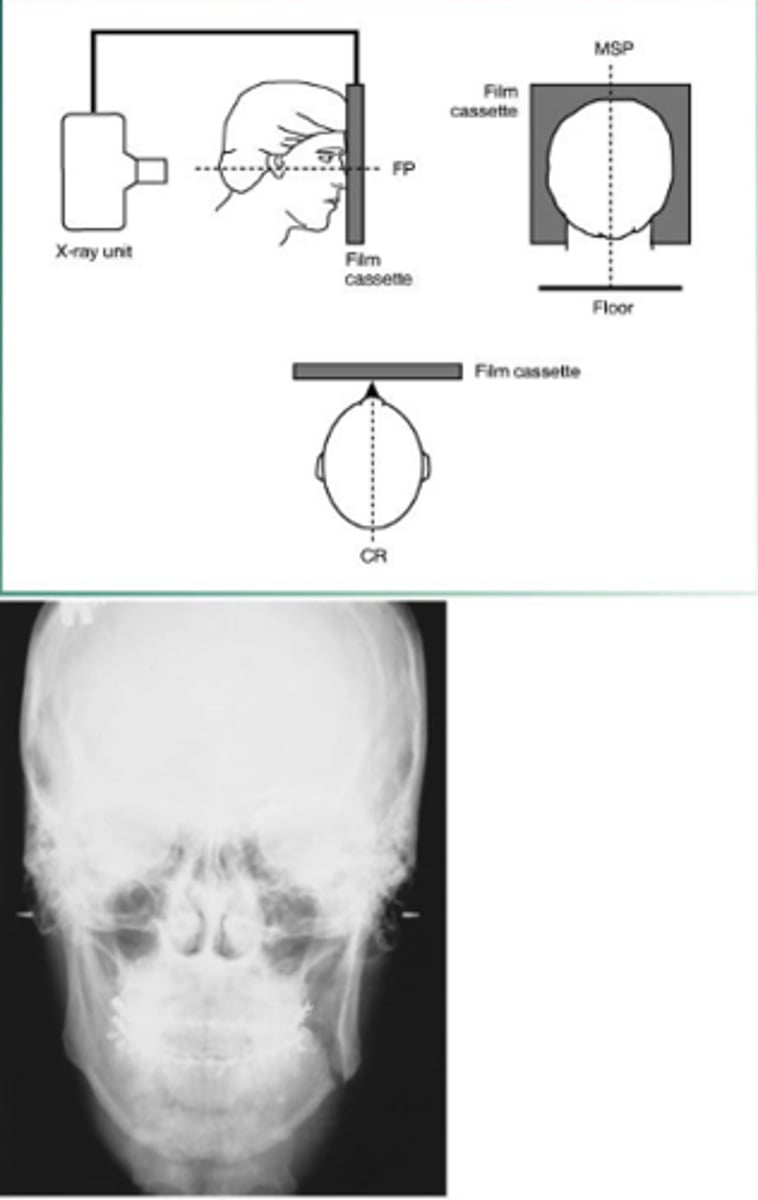

posteroanterior

evaluate facial growth and development, trauma, disease and developmental abnormalities; shows sinuses, nasal cavity, and orbits

posteroanterior projection receptor placement

long axis of receptor is vertical

posteroanterior projections head position

forehead and nose touch receptor

posteroanterior projection beam alignment

centered over receptor

parallel to receptor